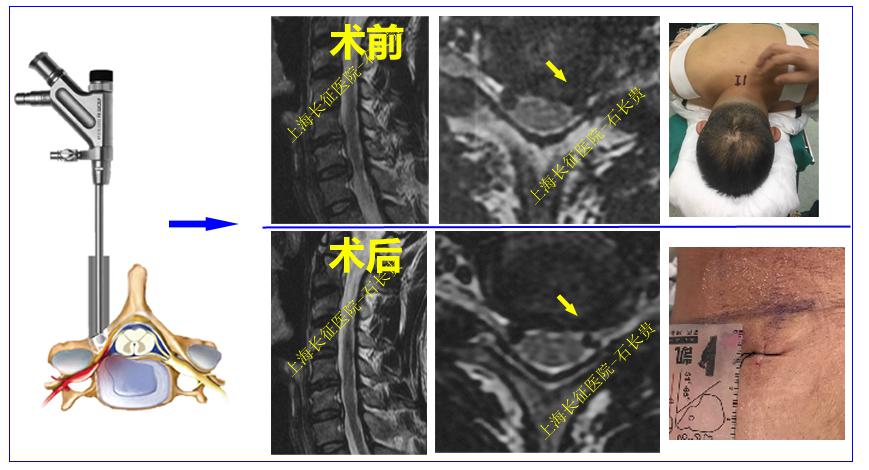

2、微创颈椎后路内镜手术: 属于颈椎微创手术范畴,适合部分神经根型颈椎病患者,主要通过颈后路1cm切口放置工作通道,在内镜下摘除压迫神经根的椎间盘和骨赘。这种手术方式更加微创(损伤更小、出血更少),不需安装钢板等内植物,术后第2天即可出院。